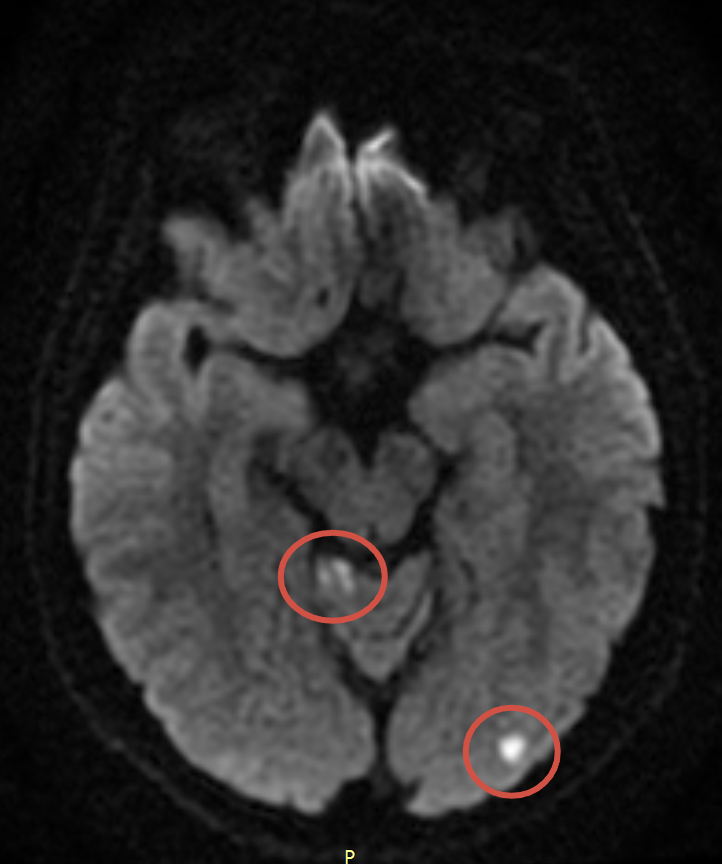

В отделение экстренной помощи поступил пациент 40 лет. Накануне он выполнял физическую нагрузку, после чего прилёг на кровать. При попытке встать с кровати внезапно возникли звон в ушах, головокружение, боль в области шеи, тошнота, рвота и расфокусировка зрения. Со временем жалобы постепенно регрессировали.

При проведении магнитно-резонансной томографии головного мозга выявлены множественные очаги острого ишемического инфаркта в вертебро-базилярном бассейне с обеих сторон.